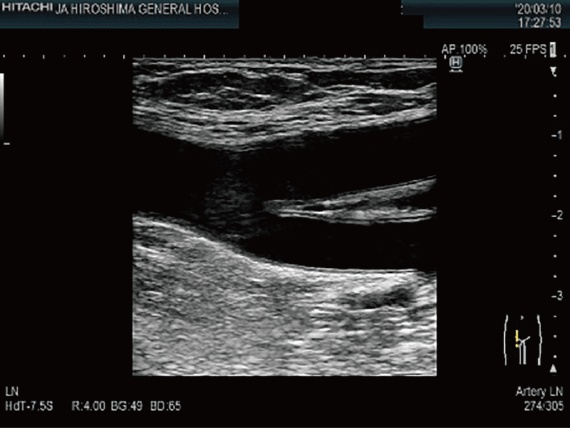

頸動脈超音波検査

胸頸部より超音波を照射し,頸動脈を観察する検査です。動脈硬化やプラークによる血管狭窄・閉塞などの評価に用いられます。

上肢・下肢血管超音波

上肢や下肢から超音波を照射し,動脈や静脈を観察する検査です。静脈では,エコノミークラス症候群に代表される静脈内血栓や静脈瘤の評価に用いられます。動脈では,動脈硬化の程度や血管狭窄・閉塞などの評価に用いられます。